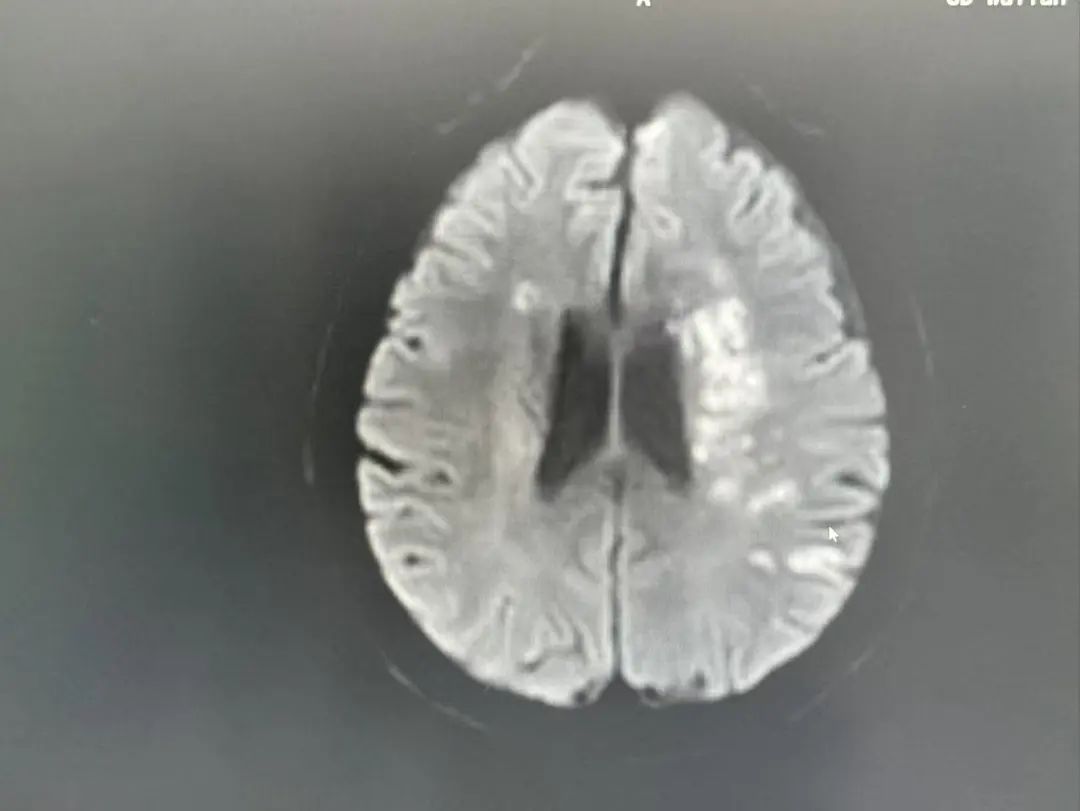

"左侧大脑中动脉闭塞!"

头颈部CTA检查揭开了更凶险的真相:

多发性脑梗死:左侧大脑关键区域受损

血管危机:左侧大脑中动脉闭塞,血流几乎中断

罕见盗血现象:锁骨下动脉重度狭窄,导致血流“偷走”了脑部的供血